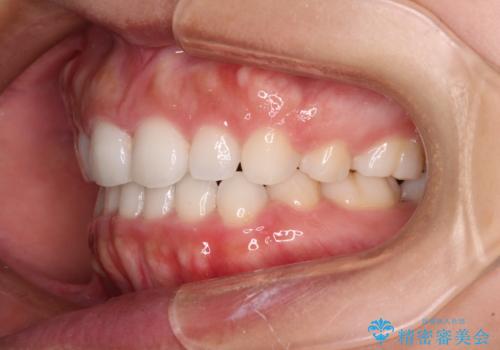

- 口元の突出感を気にして来院された患者様です。

上下左右の第一小臼歯4本を抜歯して口元を下げる治療計画としました。

表側のワイヤー矯正に比べると治療期間は長く、費用も高額となりますが、どうしても目立たせたくないという方にはお勧めの抜歯矯正です。